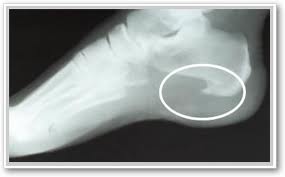

- Heel spurs

Heel spurs- Spurs are a result of excessive / malaligned bone growth. Prolotherapy (PROliferation) is supposed to add tissue to the injured site to make it “stronger.” So, for an issue where we already have too much tissue, the solution is a treatment which is supposed to add more tissue?